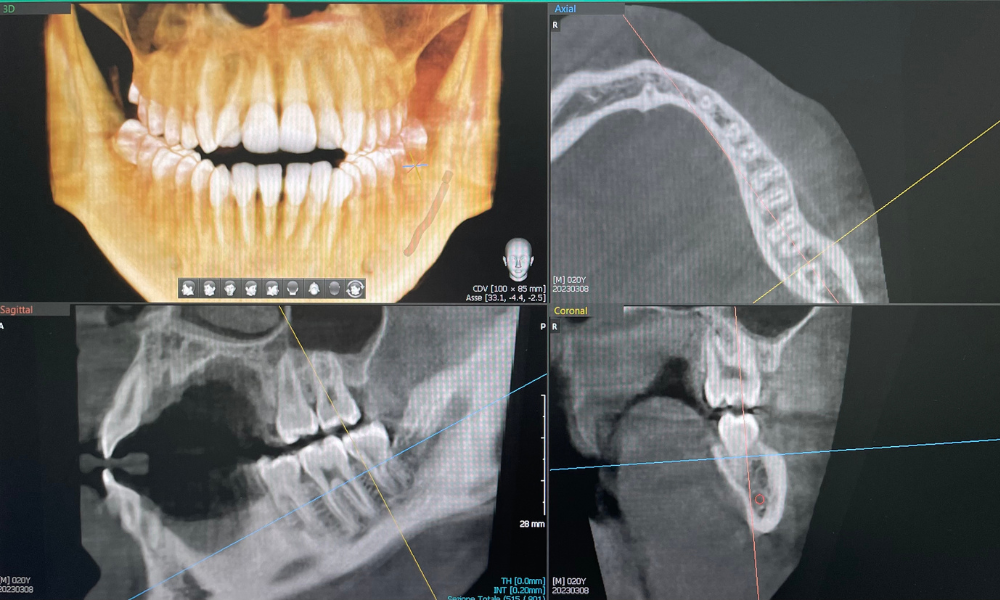

CBCT (Cone Beam Computed Tomography)

La CBCT (Cone Beam Computed Tomography) è una tecnica di imaging che sfrutta un fascio conico di radiazioni per ottenere immagini tridimensionali dell’anatomia dentale e ossea. Grazie a questa tecnologia, possiamo eseguire diagnosi accurate e pianificare interventi complessi con grande precisione, come l’implantologia. La CBCT è particolarmente utile per la valutazione del posizionamento degli impianti, dei denti inclusi e delle patologie ossee, offrendo un livello di dettaglio e di comfort superiore alle tecniche tradizionali.